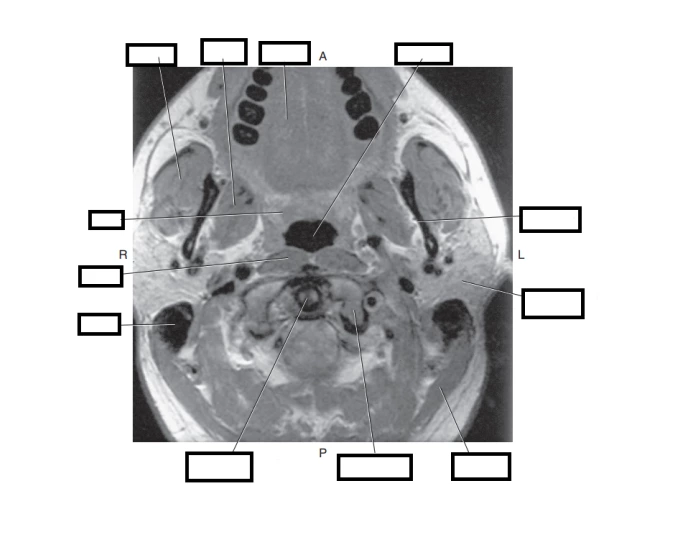

These changes warrant the need for medical professionals to under stand and identify human anatomy in both 2D and 3D images. Sectional anatomy emphasizes the physical relationship between internal structures. Cross Sectional Anatomy, Timothy F. Dutra, human anatomy, anatomical sections, CT scan, computed axial tomography, MRI scan, magnetic resonance imaging, virtual

Figure 7 - Cross-sectional anatomy-thigh: Muscles, Nerves The Visible Human Project is a fantastic tool that allows you to view almost all anatomical structures of the body. The Visible Human Project Overview The NLM Visible Human Project has created publicly-available complete, anatomically detailed, three-dimensional representations of a human male body and a human female body. Specifically, the VHP provides a public-domain library of cross-sectional cryosection, CT, and MRI images obtained from one male cadaver and one female cadaver. The Visible Man data set The Sectional Anatomy Study Tool is a web-based program to help the user learn human anatomy through images produced by CT-scan (computed tomography) and MRI (magnetic resonance imaging). The user can easily navigate through the stacks of image "slices" of each body section. The label "on" / "off" feature provides users an opportunity for self-assessment.…